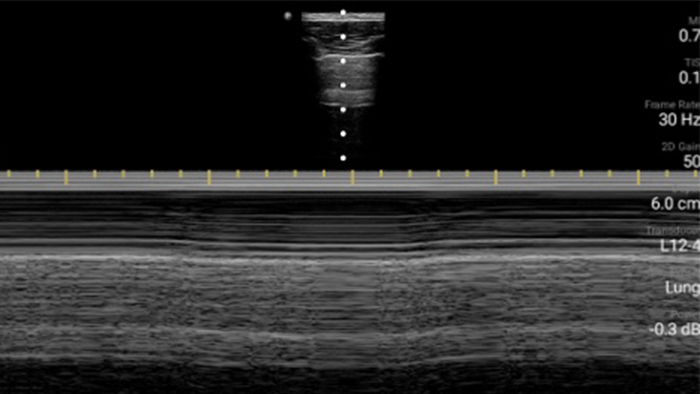

Utilice Lumify para la evaluación de las vías respiratorias y pulmonares

Las soluciones Lumify POCUS pueden ayudarle a detectar el tubo endotraqueal dentro de la tráquea, ayudar en los procedimientos de cricotirotomía emergentes, en el diagnóstico de derrame pleural y enfermedades alveolares intersticiales.

Transductor de matriz lineal de banda ancha Lumify L12-4